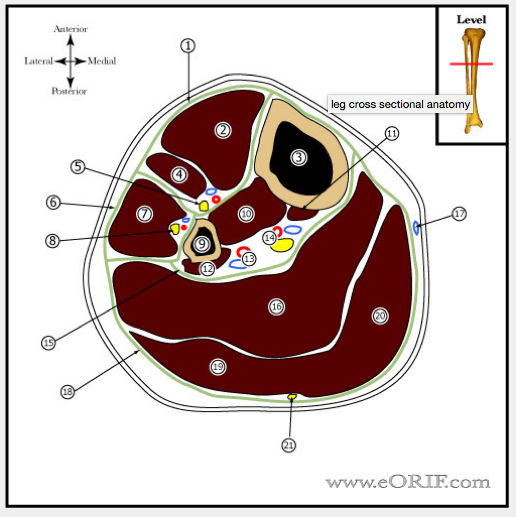

Name the following strucutres

1: anterior compartment

2: tib ant

3: tibia

4: EDL

5: deep peroneal & tibial vessels

6: lateral compartment

7: peroneus longus

8: superficial peroneal nerve

9: fibula

10: tib post

11: FDL (comes off tibia)

12: FHL (comes off fibula)

13: peroneal vessels

14: tibial nerve and posterior tibial vessels

15: deep posterior compartment

16: soleus

17: long saphenous vein

18: superficial posterior compartment

19: Lateral head of gastrocnemius

20: medial head of gastroc

21: sural nerve and lesser saphenous vein